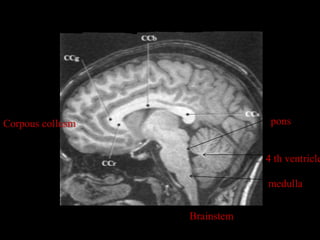

Corpous collusm                pons

4 th ventricle

medulla

Brainstem

Corpous collusm pons 4 th ventricle medulla Brainstem